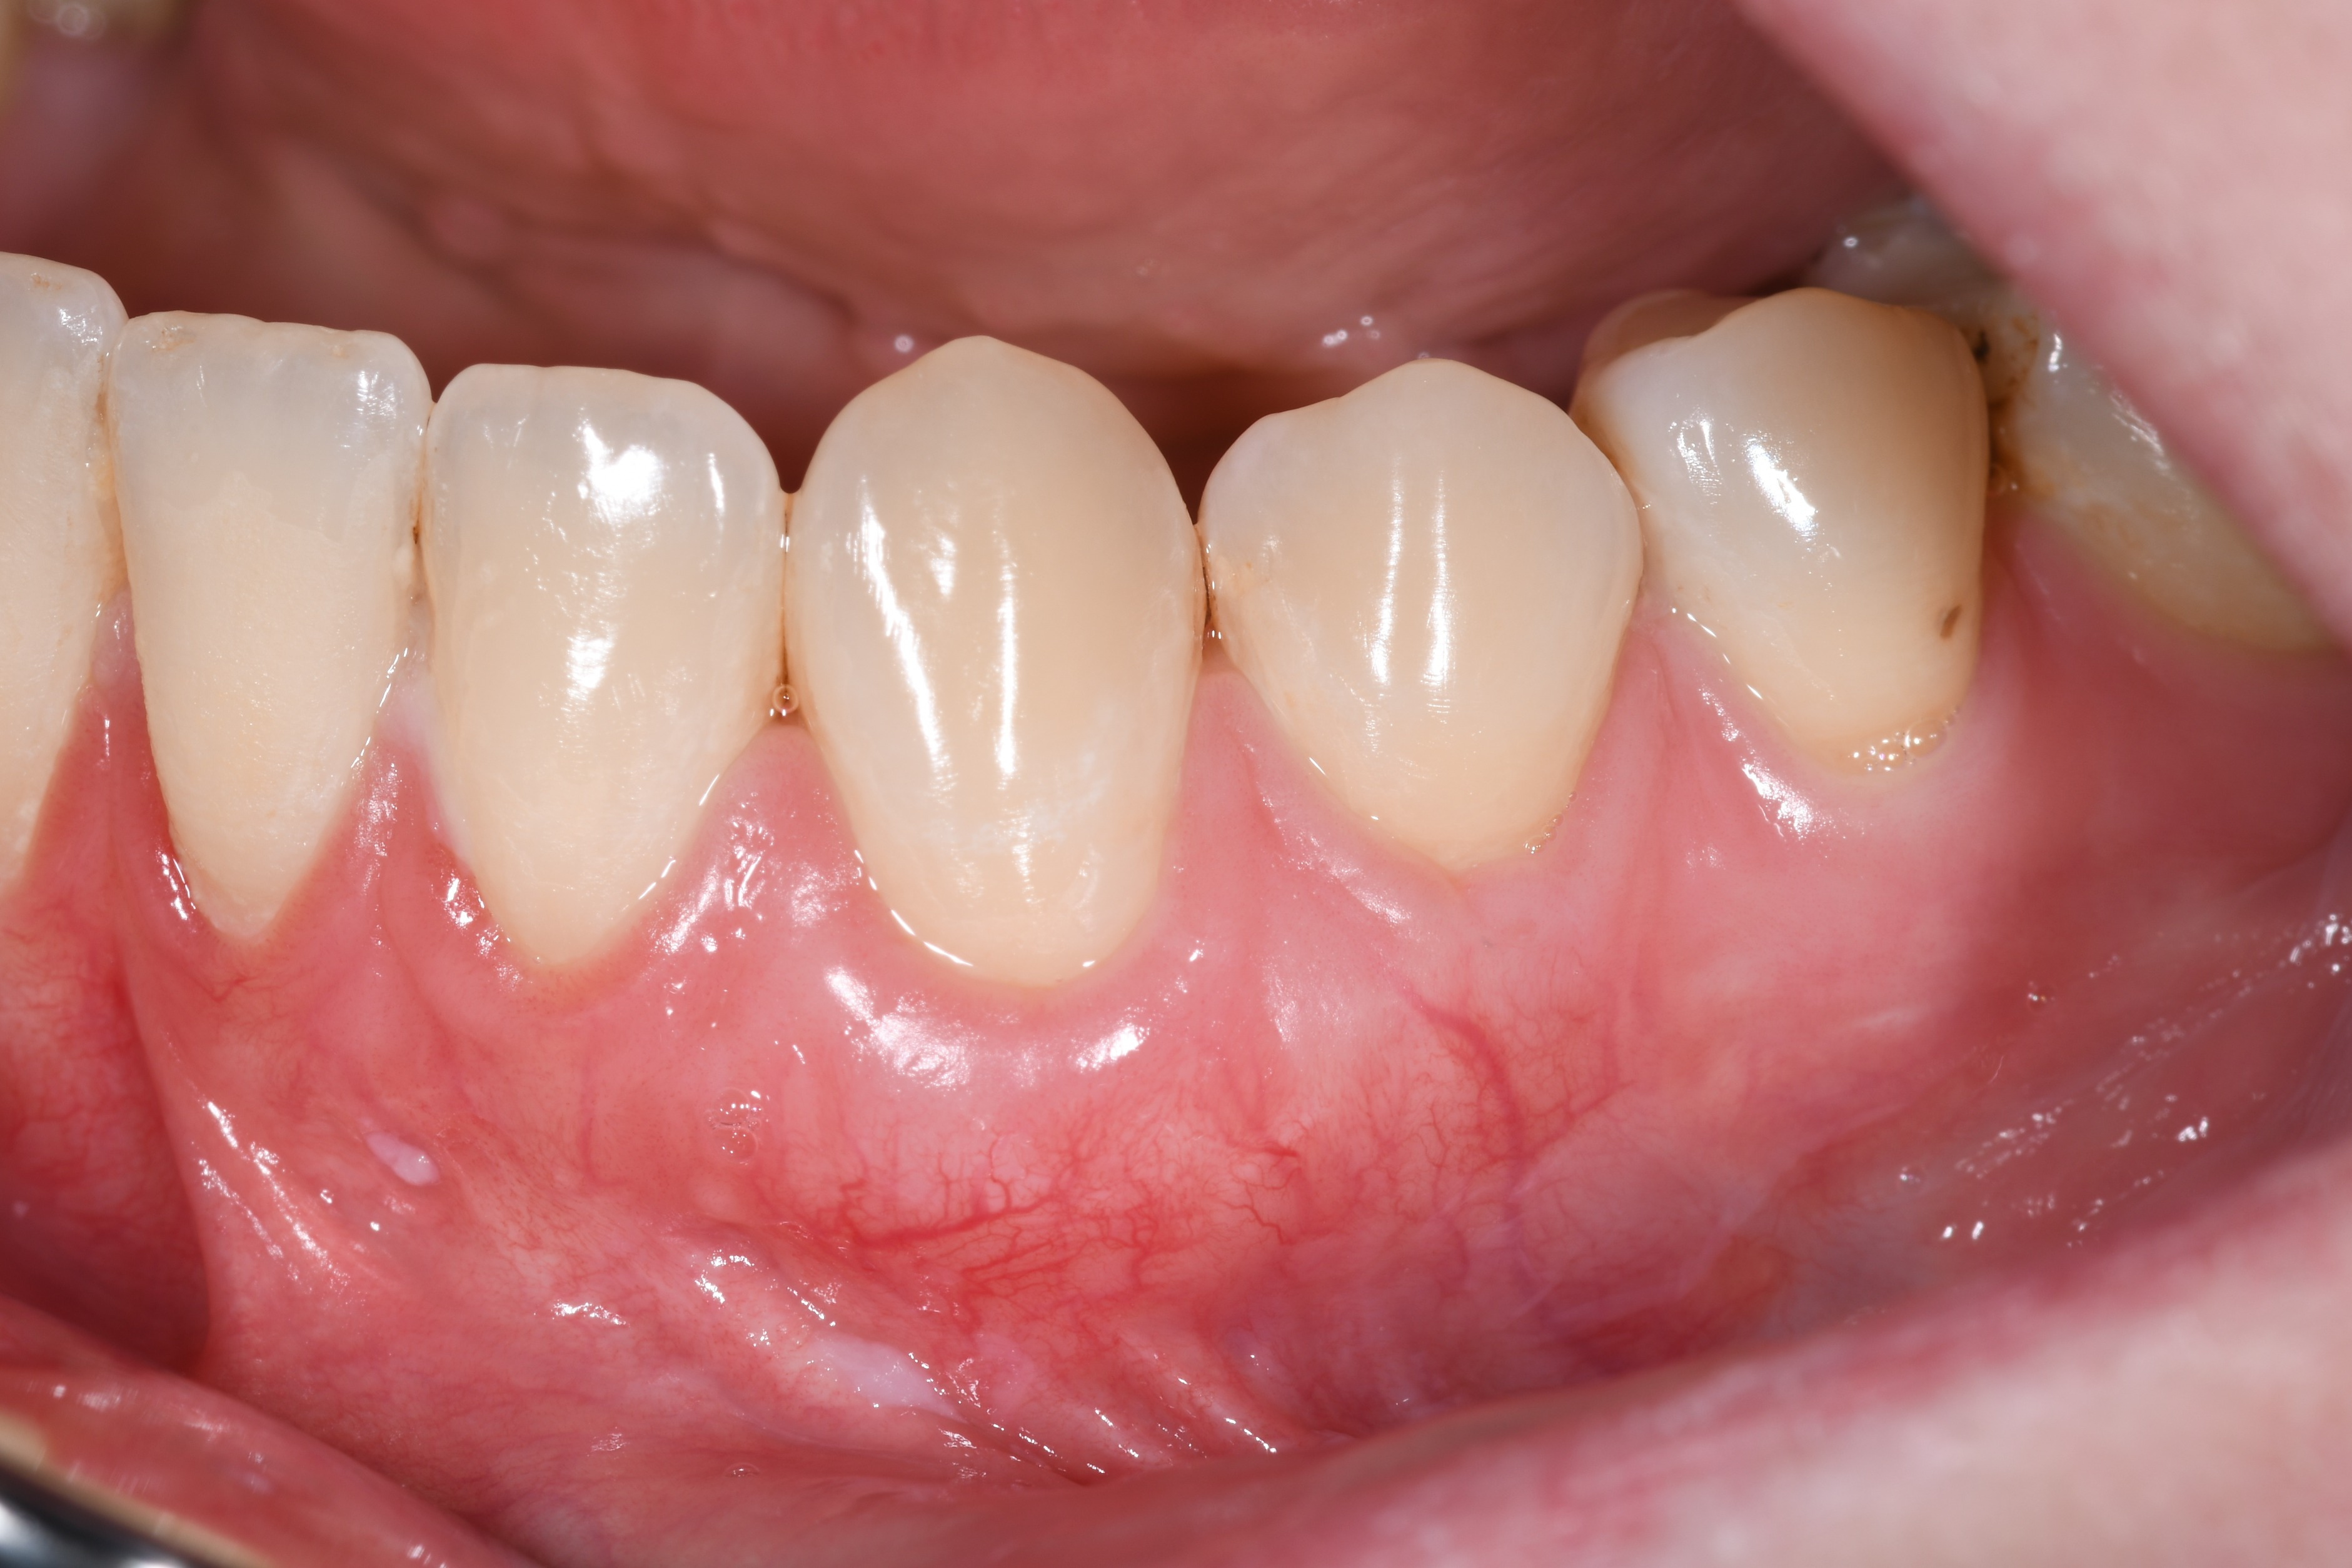

Prekrivanje recesija gingive spada u visoko specijalizirane mikrokirurške zahvate u parodontologiji.Osim samog prekrivanja recesije važna je i kvaliteta gingive oko zuba(pričvrsna gingiva). Predvidljivost rezultata nakon operacije ovisi o tipu i zahvaćenosti recesije.

Ovdje je prikaz slučaja operativnog zahvata recesije(Miller klasa 1) i situacija 2. godine nakon zahvata.